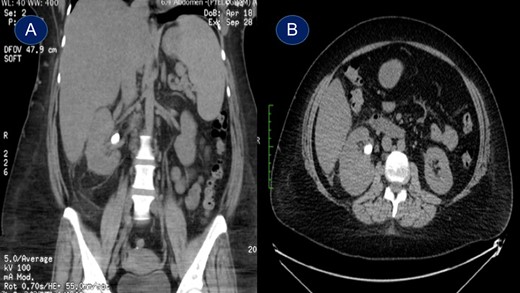

This is a 45-year-old female patient known to have diabetes mellitus and old cerebrovascular attack presented with right flank pain. Laboratory investigations revealed normal WBC count with a hemoglobin 10.4 mg/l. Radiological investigation showed right a 20 mm right renal stone (Fig. 1). Patient underwent FURS-L using a 10/12Fr Ureteral Access sheath. We did endoscopic renal exploration plus laser lithotripsy using Flex-Xc STORZ. The irrigation was under hydrostatic pressure of 80 cm H2O. The procedure was uneventful with an operative duration of 88 minutes. However, severe extravasation was noted at the end (Fig. 2). Six hours postoperatively the patient started to have high grade fever with a sudden drop of hemoglobin level to 6.6 mg/l. Immediate abdominopelvic CT scan with contrast was carried out showing severe right subcapsular renal hematoma. This complication was managed conservatively through proper antibiotics, blood transfusion and good hydration for 7 days. The patient was seen in the outpatient clinic 2 months later with a new abdominopelvic CT scan which showed a regression of subcapsular renal hematoma and surprisingly migration of stone fragments into the regressed subcapsular hematoma (Fig. 3). On the other hand, the upper urinary tract was free of stones.

Plain abdominopelvic CT, coronal view showed migrated stone fragments into the regressed right subcapsular renal hematoma.